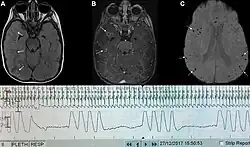

| Graph showing ataxic respirations and other pathological breathing patterns. | |